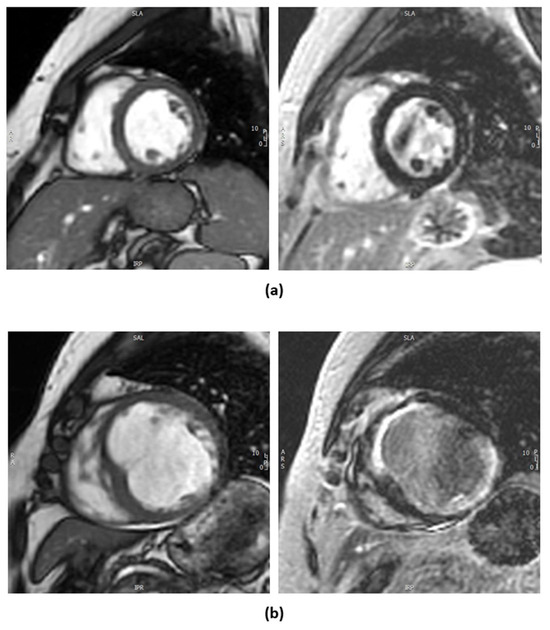

1.2.2. Cardiac Magnetic Resonance Imaging

| Cardiac MRI (CMRI) | Identifies scar burden by measuring contrast uptake in extracellular space. | High spatial resolution. No ionizing radiation. | Expensive. Requires expertise. Not suitable for all patients (e.g., claustrophobia, metal implants). |